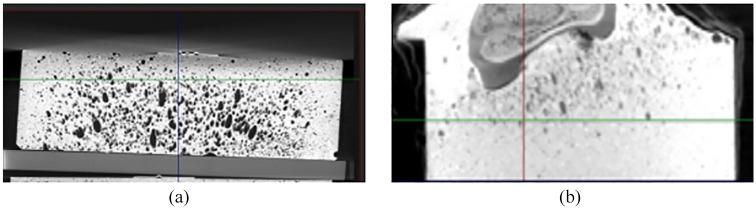

Bone cement is often used, in experimental biomechanics, as a potting agent for vertebral bodies (VB). As a consequence, it is usually included in finite element (FE) models to improve accuracy in boundary condition settings. However, bone cement material properties are typically assigned to these models based on literature data obtained from specimens created under conditions which often differ from those employed for cement end caps. These discrepancies can result in solids with different material properties from those reported. Therefore, this study aimed to analyse the effect of assigning different mechanical properties to bone cement in FE vertebral models. A porcine C2 vertebral body was potted in bone cement end caps, CT scanned, and tested in compression. DIC was performed on the anterior surface of the specimen to monitor the displacement. Specimen stiffness was calculated from the load-displacement output of the materials testing machine and from the machine load output and average displacement measured by DIC. Fifteen bone cement cylinders with dimensions similar to the cement end caps were produced and subjected to the same compression protocol as the vertebral specimen and average stiffness and Young moduli were estimated. Two geometrically identical vertebral body FE models were created from the CT images, the only difference residing in the values assigned to bone cement material properties: in one model these were obtained from the literature and in the other from the cylindrical cement samples previously tested. The average Youngs modulus of the bone cement cylindrical specimens was 1177 ± 3 MPa, considerably lower than the values reported in the literature. With this value, the FE model predicted a vertebral specimen stiffness 3% lower than that measured experimentally, while when using the value most commonly reported in similar studies, specimen stiffness was overestimated by 150%.

在实验生物力学中,骨水泥常被用作椎体的灌封剂。因此,它通常被纳入有限元(FE)模型中,以提高边界条件设置的准确性。然而,骨水泥的材料特性通常是根据从在与用于水泥端盖的条件不同的条件下制作的标本获得的文献数据分配给这些模型的。这些差异可能导致实体的材料特性与报道的不同。因此,本研究旨在分析在有限元椎体模型中为骨水泥分配不同力学性能的影响。将一个猪的C2椎体灌封在骨水泥端盖中,进行CT扫描,并进行压缩测试。在标本的前表面进行数字图像相关(DIC)以监测位移。根据材料试验机的载荷-位移输出以及通过DIC测量的机器载荷输出和平均位移来计算标本的刚度。制作了15个尺寸与水泥端盖相似的骨水泥圆柱体,并对其进行与椎体标本相同的压缩试验方案,并估计其平均刚度和杨氏模量。从CT图像创建了两个几何形状相同的椎体有限元模型,唯一的区别在于分配给骨水泥材料特性的值:在一个模型中,这些值来自文献,而在另一个模型中,这些值来自先前测试的圆柱形水泥样品。骨水泥圆柱形标本的平均杨氏模量为1177±3MPa,远低于文献报道的值。使用这个值时,有限元模型预测的椎体标本刚度比实验测量值低3%,而当使用类似研究中最常报道的值时,标本刚度被高估了150%。